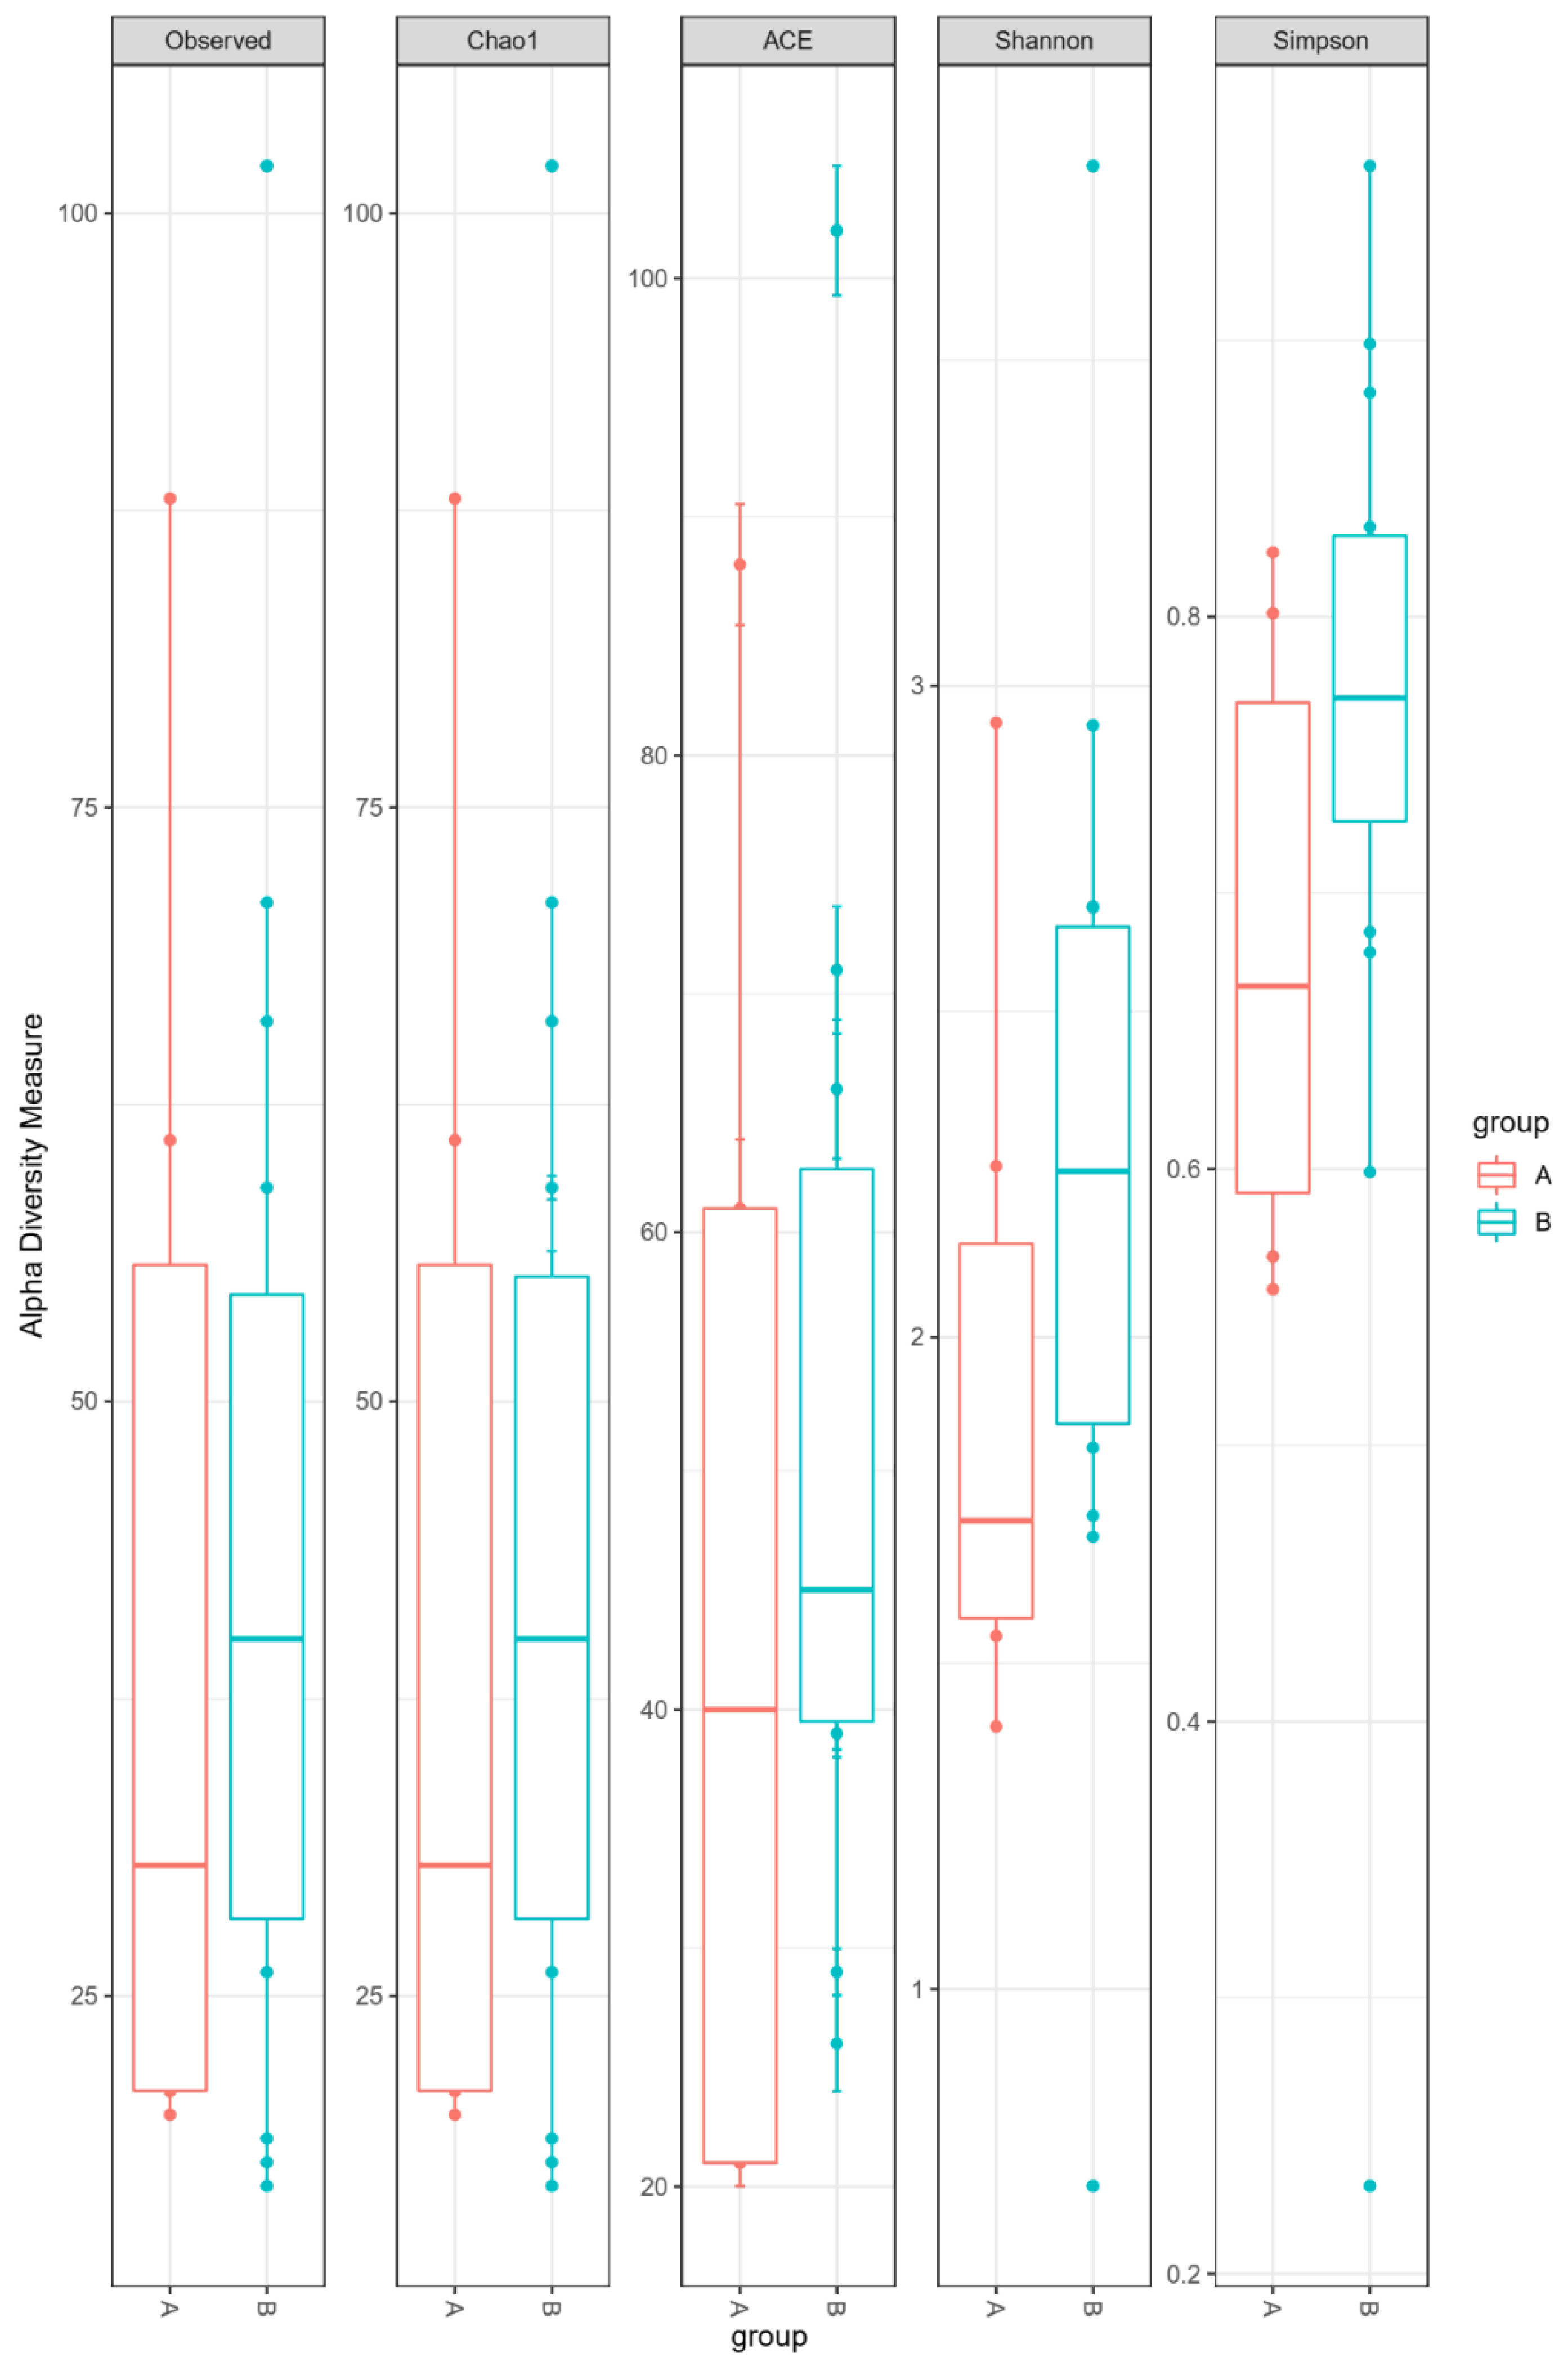

3.2. Sequencing Data